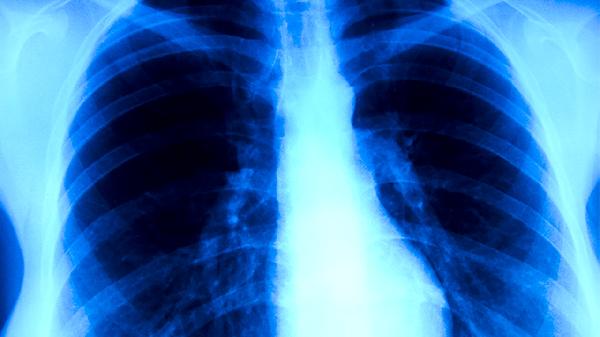

穩(wěn)定期患者可逐步進行有氧運動如散步、太極拳,改善肺通氣功能。存在肺纖維化者可進行腹式呼吸訓(xùn)練,使用呼吸訓(xùn)練器增強膈肌力量。康復(fù)期間需定期復(fù)查胸部CT和痰涂片,監(jiān)測病灶吸收情況及細菌學(xué)轉(zhuǎn)歸。